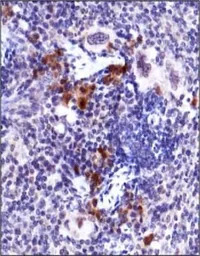

IHC-P analysis of mouse spleen tissue using GTX30636 ATM (phospho Ser1981) antibody [10H11.E12].